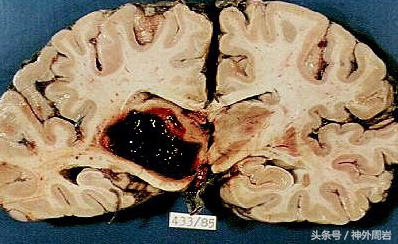

高血压是脑出血最主要的病因及重要的危险因素。长期高血压,中小动脉中膜就会出现慢性的病理改变,学术名称叫“脂质透明样变性”。高血压脑出血常常发生于脑基底节区,几率高达90%。最常累及的是豆纹动脉。脑出血之所以危害严重,是因为两项因素:一是原发性血肿的占位效应;二是继发性血肿引起的周围低灌注和水肿的危害,以及血液毒性作用。